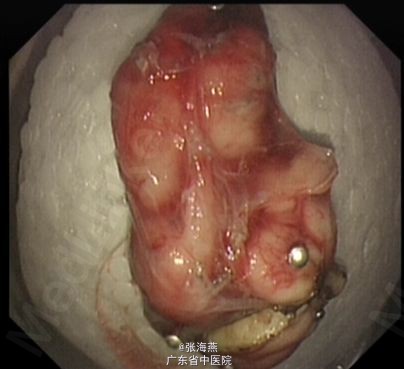

诊断:食管下段平滑肌瘤 处理:排除禁忌症后,于2013-7-23在气管插管全麻下行食管肿物ESD术,术中所见:食管距门齿35cm见隆起性肿物,大小约2.5cm×2cm,表面光滑;切除肿物拿出体外测量,大小约5.3cm×2.5cm×1cm。术程顺利,术后予静滴明可欣抗感染,泮托拉唑静滴抑酸护胃,铝镁加混悬液口服保护胃粘膜,以及补液支持治疗。术后病理提示:(食管肿物)平滑肌瘤;免疫组化结果:Vimentin(+),SMA(+),Desmin(+),CD117(—),CD34(—),Ki67(<1%+)。5天后患者病情稳定出院。